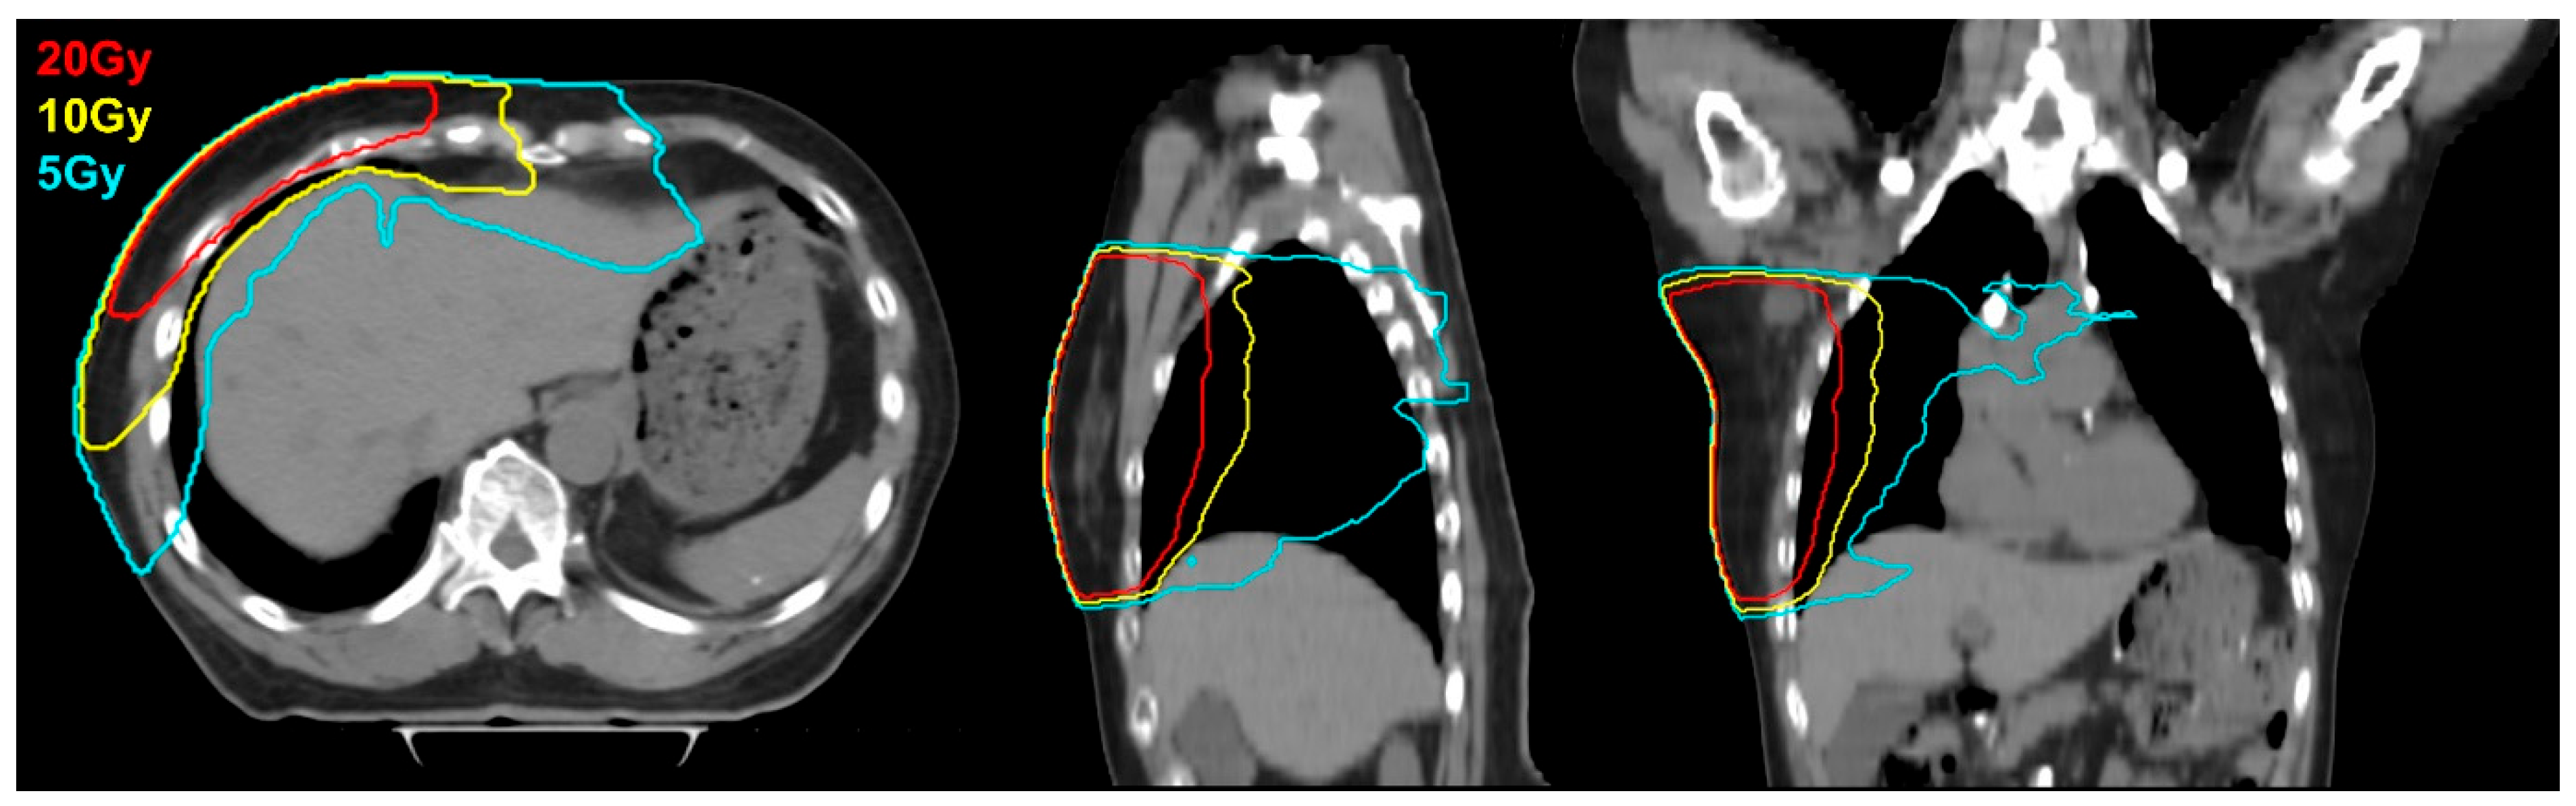

| Mean dose to liver (cGy) | 168.9 | (0.8–984.1) |

| V5Gy (%) | 6.1 | (0–83.7) |

| V10Gy (%) | 0.75 | (0–33.0) |

| V20Gy (%) | 0.04 | (0–12.35) |